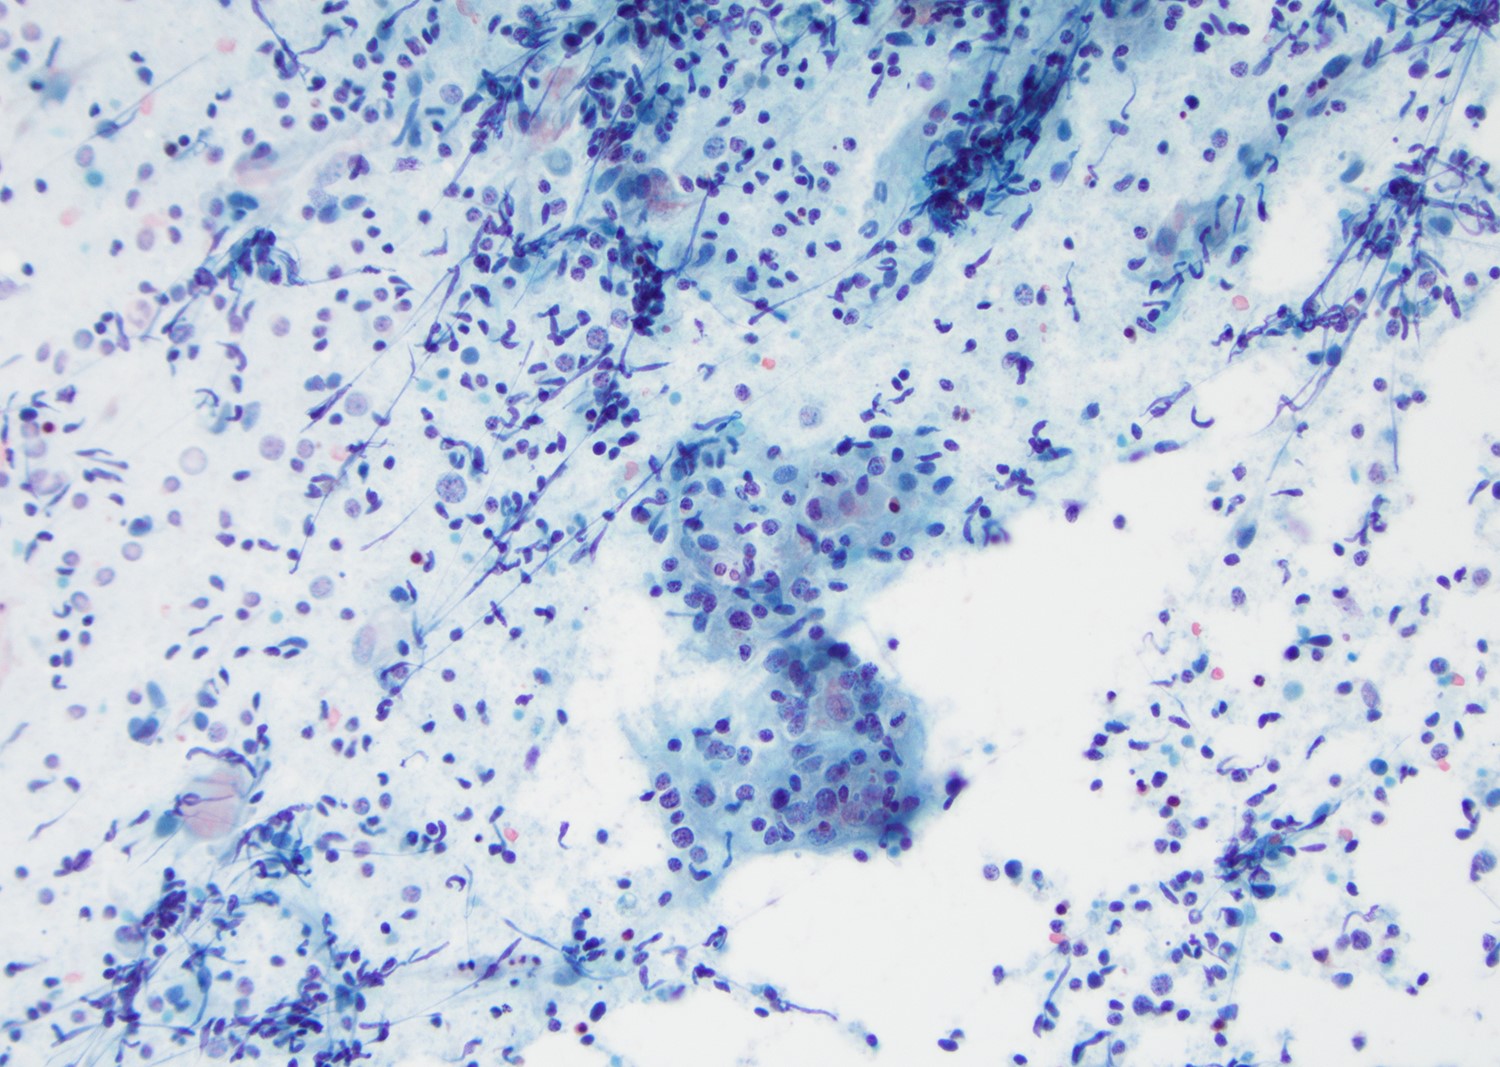

Cytology description

- Mature nucleated squamous cells with variable reactive atypia, anuclear cells and squamous epithelium (Int J Surg Case Rep 2017;41:383, Diagn Cytopathol 2012;40:684)

- Polymorphous lymphocytes and aggregates of epithelioid histiocytes

- Proteinaceous background

- Variable presence of acute inflammation, and bland appearing mucinous ductal cells and ciliated columnar cells

- Scant cellularity, abundant proteinaceous background, lack of squamous cells and epithelial cells, marked atypia of epithelial cells, abundance of lymphocytes pose diagnostic challenges

Cytology images